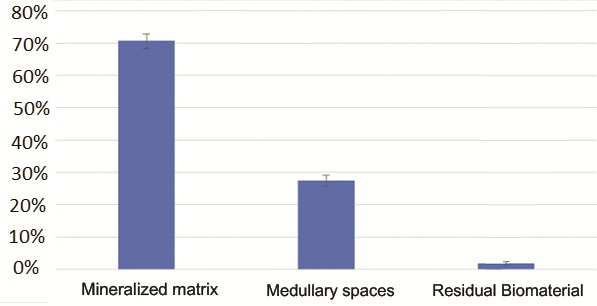

Гістологічний аналіз показав добре організовану, в основному зрілу тканину, утворену компактною пластинчастою кісткою, що характеризується чітко окресленими кістковими пластинками навколо каналів Гаверсіяна та Фолькмана, оточених меншими ділянками, в яких пластинки були менш організованими та багатими остеоцитами на стадії дозрівання . Кількість знайденої мінеральної матриці - від 69% до 72% - була особливо значною.

Рис. 12 – Гістоморфометричне дослідження. Мінералізований кістковий матрикс займає приблизно 70% зразка. Залишковий біоматеріал становить менше 2%.